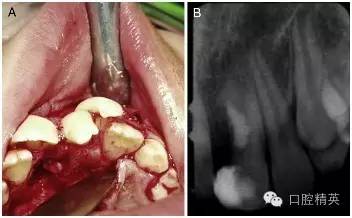

口腔外科手術(shù)方案是將融合牙齒的近中部分與遠(yuǎn)中部分盡可能地從冠方向根方劈開,然后拔除近中較小的部分。

手術(shù)在局麻下進(jìn)行,無術(shù)前用藥,也沒有對(duì)口腔進(jìn)行其他特殊的術(shù)前準(zhǔn)備。為了分牙的便利,患牙唇頰側(cè)的牙齦黏膜都被切至骨膜進(jìn)行了徹底的翻瓣(圖 2-A)。

為了劈開牙冠和部分牙根,一把鋒利的骨鑿被順著牙長軸方向并稍向遠(yuǎn)中傾斜地放置在了融合牙切端的發(fā)育溝中。在錘子的猛擊下,這顆過大牙齒的多生部分被逐漸劈離出來。按照術(shù)前計(jì)劃,并通過術(shù)中調(diào)整骨鑿的傾斜度,分離的剖面最終被止于齦下。

分牙過程中,在牙根中 1/3 處出現(xiàn)了一個(gè) 4mm 范圍的橢圓形的洞,通過洞可以觀察到暴露的牙髓。牙體牙髓醫(yī)生立即用 MTA 和調(diào)拌刀對(duì)這個(gè)洞進(jìn)行了修補(bǔ)和拋光(圖 2-B)。翻瓣縫合之前,口腔外科醫(yī)生對(duì)尖銳的骨刺進(jìn)行了修整,以便縫合后的牙齦黏膜能夠與硬組織緊密地貼合在一起。

圖 2 手術(shù)過程。(A)為了方便劈牙,對(duì)唇腭側(cè)牙齦黏膜做了徹底的翻瓣。(B)多生牙部分劈開拔除后和 MTA 蓋髓后的 x 線根尖片。